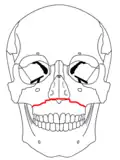

| Fraturas 1 de Le Fort | |

No início do século XX, René Le Fort mapeou as regiões faciais típicas dos traumas maxilo faciais, agora conhecidos como Fraturas I, II, e III de Le Fort (direita).[11] A Fratura I de Le Fort, também chamada de Fratura de Guérin ou Fratura transversa,[12] envolve a maxila, separando-a do palatino.[13] A Fratura II de Le Fort, conhecida também como Fratura piramidal,[12] atravessa os ossos nasais e o aro orbital.[13] A Fratura III de Le Fort, por sua vez, chamada também de Disjunção crâniofacial,[12] atravessa a frente da maxila e envolve as suturas zigomaticofrontal, maxilofrontal nasofrontal, os assoalhos das órbitas, a etmóide e o esfenóide.[12] As Fraturas de Le Fort, responsáveis por 10-20% das fraturas faciais, são frequentemente associadas com outros ferimentos graves.[13] Le Fort fez seu trabalho com base em cadáveres e caveiras, e o sistema de classificação tem sido criticado como impreciso e simplista uma vez que a maioria das fraturas de meia-face envolvem uma combinação das fraturas de Le Fort.[13] Embora a maioria das fraturas faciais não seguem os padrões descritos por Le Fort, seu sistema ainda é utilizado para categorizar os diversos tipos de traumatismos.[14] http://www.angelfire.com/nm/cirurgia/pritra/Image90.gif